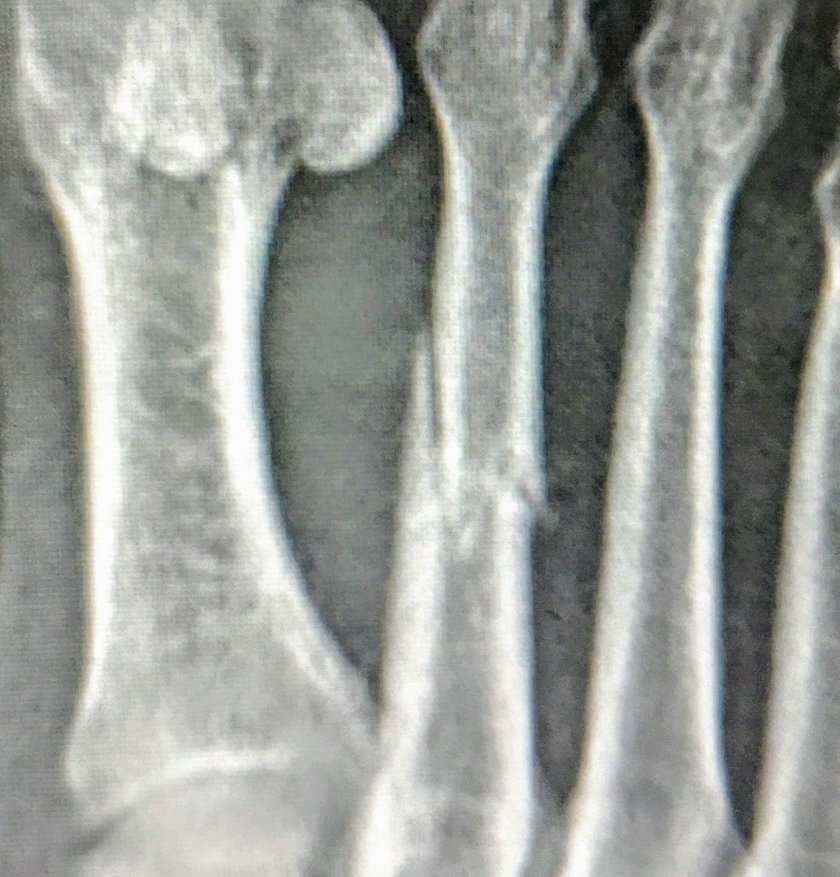

Da mein Fuss seit letztem Donnerstag nicht mehr wirklich besser wurde, hab ich mich entschlossen einen Arzt aufzusuchen. Nach 2 Std Bürokrieg, hat mir die Ärztin nach kurzer Untersuchung beschieden, es müsse ein Röngenbild her. Ich konnte dann am nächsten Morgen um 8.00 zum Röntgen. Nach kurzem Blick auf die Bilder, zusammen mit der Ärztin, konnte ich die Diagnose auch selber stellen:

Gebrochener Mittelfuess Knochen am 2. Zehen von links. 6 Wochen Stützschiene.